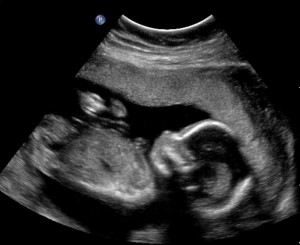

This morning was kind of a big moment for us as Rick and I went for our second baby’s sonogram. They do all sorts of measurements of the baby’s anatomy. They look to be sure the organs are developing and so forth. Of greatest interest to us was finding out the gender of this new little one.

Apparently, this little one did not want to move HIS legs apart very much. So it took some time for the technician to tell us that we are going to have another baby boy. Quin just looked at me when I told him that he was going to have a baby brother. We are all excited. Just a few more months before he will make his debut. So let the name suggestions begin funneling our way. We’ve got time to consider them all.